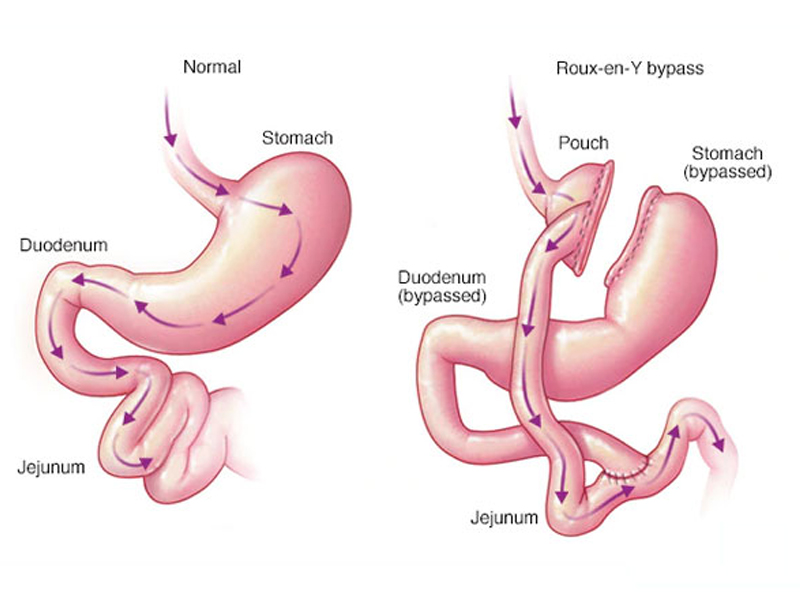

Bariatric Surgery

Gastric bypass and other weight-loss surgeries make changes to your digestive system to help you lose weight by limiting how much you can eat or..